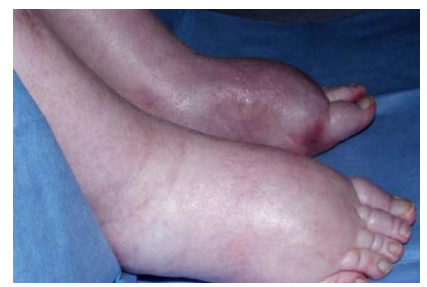

pedal odema

Pulmonary throboemboli